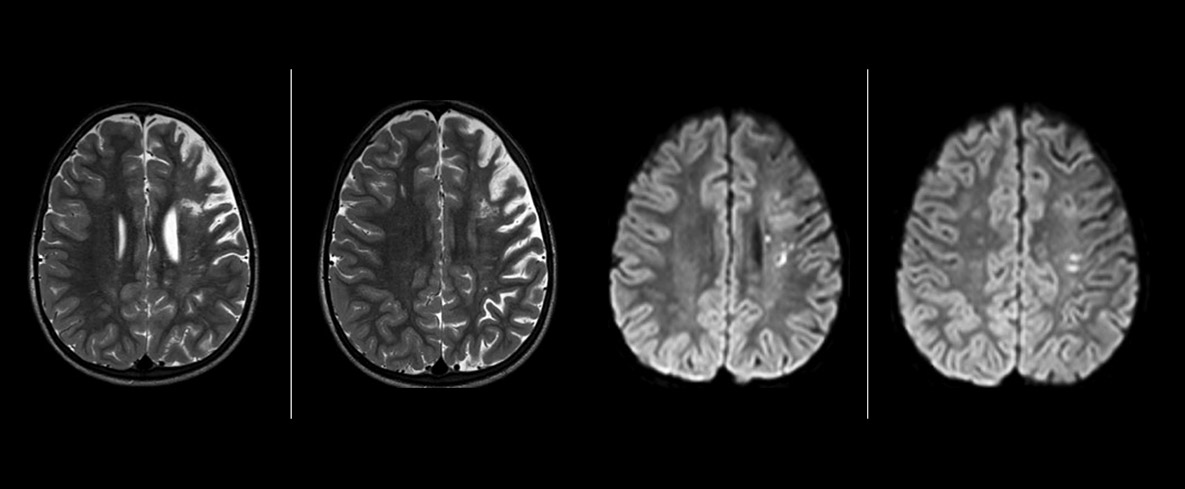

The value of susceptibility weighted imaging in visualizing brain injury is well documented. The Philips multi-echo SWIp technique provides fast susceptibility weighted imaging with enhanced susceptibility contrast and high resolution.

“SWIp helps us identify blood or blood products, calcification, and diseases that affect the vascular system,” says Dr. Miller. “In children with traumatic brain injuries, it highlights areas that are injured, better than some of the previous techniques that we were using. These children often have micro-injuries that cause small amounts of blood or tissue damage. Adding SWIp helps us to better characterize the extent and nature of the injury. Having characterized an injury to the extent of what’s possible supports our diagnostic confidence.”

“I would definitely recommend other users to implement SWIp. We initially added the SWIp sequence following a lot of support for its utility in the literature. Then we directly compared SWIp to the 2D gradient echo sequences that we were using. After a good amount of clinical experience in seeing its benefits, we were confident to replace the old sequences with SWIp. It gives us a better assessment of the physiological processes of the brain that were less apparent on our previous imaging sequences,” says Dr. Miller. “SWIp is now a routine sequence for imaging traumatic brain injury patients at PCH, and it’s episodically added for patients who have intracranial vascular abnormalities.”

“I believe SWIp is rapidly becoming the standard in imaging traumatic brain injury, because of its high sensitivity to venous blood products. SWIp may even help attract patients; our neurosurgeons often ask to have the patients imaged on our scanners with highly sensitive techniques like SWIp. There’s also a growing application of SWI sequences in other vascular abnormalities because of the possibilities around physiological assessment of the brain than just a standard structural imaging.”